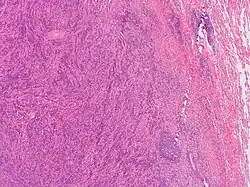

General image of plasma cell granuloma that was classified in a broader category of inflammatory pseudotumor. Original author of image was: Yale Rosen from USA[9]

PCGs were first discovered and described in 1973 by Bahadori and Liebow.[1] PCGs are characterized by the proliferation and infiltration of different inflammatory cells with the main cell observed in highest concentrations being plasma cells.[1][2] More specifically, PCGs are a type of mass-forming lesion arising from the accumulation of polyclonal plasma cells surrounded in a swirling storiform orientation of fibrosis and spindle cell proliferation.[3][4] It has been noted that these granulomas have the propensity to manifest on any organ or soft tissue.[3] Plasma cell granulomas are generally found to be benign, but in some cases, the granulomas have the ability to initiate malignancy and become symptomatic regardless of location or size.[3] Common sites of plasma cell granulomas are in the oral gingiva, lungs, vagina, larynx, orbit, spinal cord meninges, breast, pelvic soft tissue, bladder, mesentery, retroperitoneum, kidney, lymph nodes, spleen, pancreas, liver, stomach, heart, thyroid, and trachea.[1][4][5] Microscopically, plasma cell granulomas, demonstrate a lesional pattern of inflammatory pseudotumor.[1] The term inflammatory pseudotumor has previously been used to classify plasma cell granulomas. However, this term has become more uncommon in recent years due to its lack of specificity.[3] Today, scientist use more up to date diagnostic and medical terminology to avoid classifying lesions in the same group that are likely to have different etiologies.[3] Other names associated with plasma cell granulomas are inflammatory myofibroblastic tumor, inflammatory myofibrohistiocytic tumor, benign myofibroblastoma, pseudosarcoma, fibrous histocytoma, fibroxanthoma, xanthomatous pseudotumor, xanthogranuloma, myxoid hamartoma, and lymphoid hamartoma.[1][2][4][6][7][8]

Analyzing the changes that arise in the tissue associated with the mass-forming lesion has been found to be the most accurate and precise method for confirming the diagnosis of plasma cell granulomas. This can be achieved by taking excision biopsies of the unknown mass for examination.[4] Typically, plasma cell granulomas appear microscopically as a lesional mass consisting of an abundance of plasma cells intermingled among different inflammatory cells set in fibrous connective tissue displayed in a spiral appearance.[3][4]  Depending on the location of the plasma cell granuloma, vasculitis can be present but is not considered a confirmatory factor for diagnosis.[3] Kappa/lambda in-situ hybridization is another diagnostic test that needs to be done when trying to characterize the lesion for further confirmation.[3] Common results associated with kappa/lambda in-situ hybridization studies of PCGs are an abundant population of CD138 positive polyclonal plasma cells.[3] If instead, results show monoclonality of plasma cells it is indicative of plasmacytoma.[3]